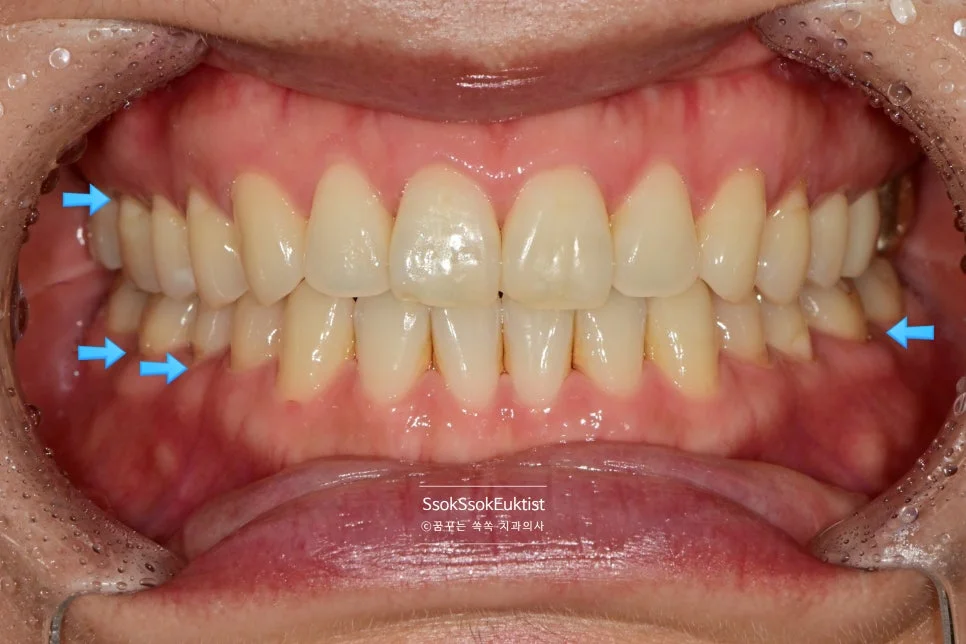

화살표로 표기된 치료 계획 — 앞쪽은 레진, 어금니는 GI

화살표로 표기된 것과 같이 눈에 보이는 앞 쪽 치아는 레진으로, 큰 어금니는 GI로 계획을 세웠는데요.